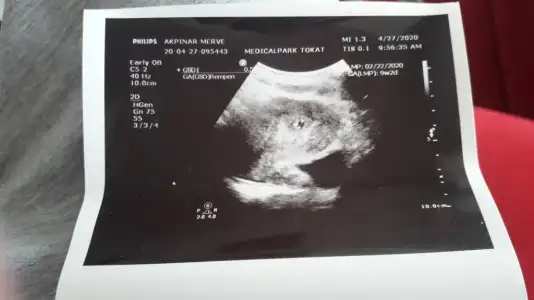

Kizlar acil yardim . Ben suan 5+1 deyim sekreter adet tarihimi yanlis girmis. Ben eve gelince fark ettim doktor haftasiyla cok uyumsuz sagliksiz olabilir dediler ultrosuna gore 9+ 2 gorunuyo strese girdim . Bununla alakasi varmidir doktorun yorumunda tekrar betama bakilcak kesenin cevresi kanli denildi

Gozun aydin canim sat tarihi tabiki cok onemli iyiki uyarmissin , haftaya ne icin cagirdi? Kalp atisi icin mi kanama icin mi?Canim cok sukur yanlislik olmus degerim 2260 cikti haftaya pazartesi tekrar cagirdi progestan hap verdi cevredeki kanama icin .Eki Görüntüle 2626129

Evet 9+2 yazıyor. Dikkat etmek lazım en ufak yalnışlık nerelere kadar götürebilir. Çok şükür çözülmüş olay.Canim cok sukur yanlislik olmus degerim 2260 cikti haftaya pazartesi tekrar cagirdi progestan hap verdi cevredeki kanama icin .Eki Görüntüle 2626129